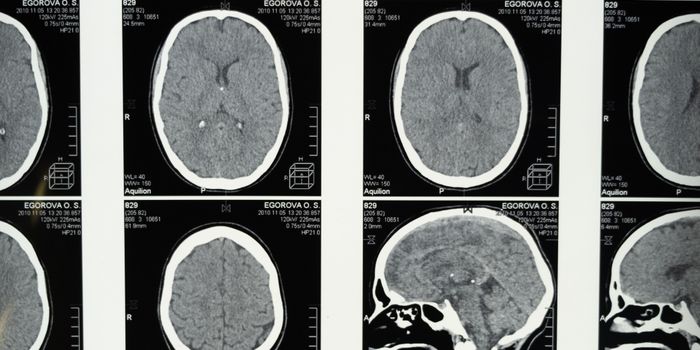

SEP 24, 2020Clinical & Molecular DXKing’s College London researchers took a closer look at emergency room CT scans of patients suspected of having a ...

DEC 04, 2015Clinical & Molecular DXIn medical emergencies like strokes, every second matters. The condition is highly time-sensitive, as survival is direct ...